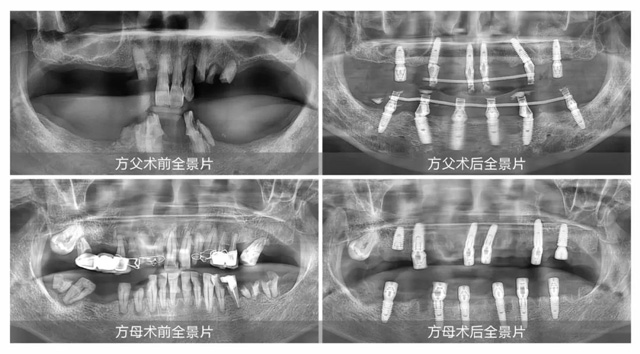

自體驗了“當天種牙當天啃雞腿”的驚喜效果后,方先生便琢磨著帶自己74歲的父親和72歲的母親種牙,但父母年紀那么大了,還能做全口種牙嗎?抱著試一試的心情,方先生帶父母到新橋口腔進行了全面的術前檢查,得到的結論是無論身體還是口腔狀況都符合臨床種植條件。

兒女們不怕出錢出力,兩老口也從善如流。2024年6月25日,方先生和弟弟,一人牽一個,陪伴父母在新橋口腔成功完成全口即刻種植。“缺牙問題不能將就,就算安假牙能省再多錢,吃東西不方便的話還是很惱火。”方先生說:“父母辛苦了一輩子,晚年安享口福是很重要的。”